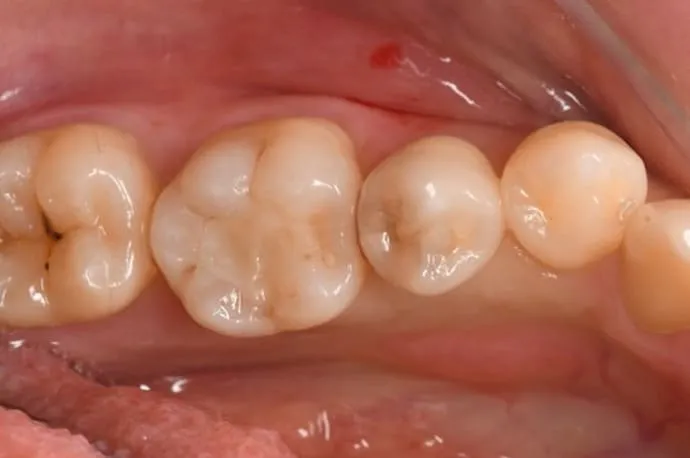

虫歯を除去した後、範囲が大きい場合は樹脂では強度不足になるため型採りを行います。歯型は歯科技工士に送り、模型をもとに詰め物を作成。問題がなければ、次回の来院時に装着します。

詰め物には、保険診療と自費診療の素材がいくつかあります。それぞれ特徴が異なりますので、患者さまのお口の状態に合った最適な材質についてはご相談ください。